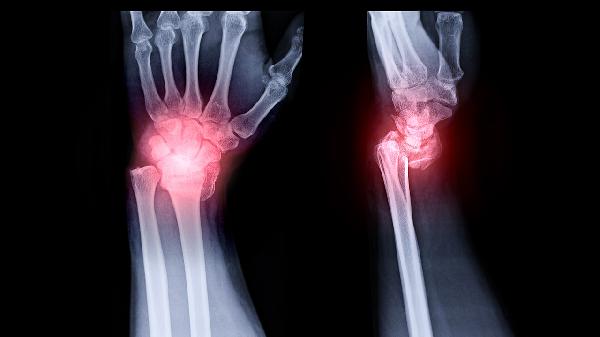

骨折后血肿机化不良或反复轻微外伤可能诱发创伤性骨囊肿。病变区常有骨膜反应,CT显示囊壁不规则。急性期需制动患肢,疼痛明显者可短期服用塞来昔布胶囊,合并感染时需联用头孢克洛分散片进行抗炎治疗。